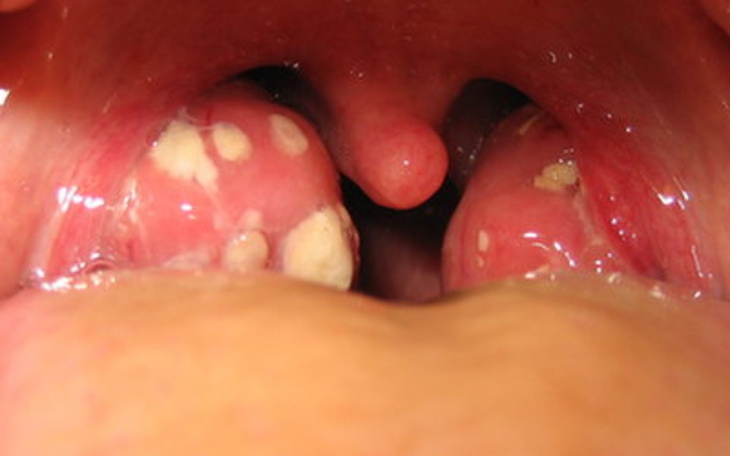

Nazywam się Anita i zbieram pieniądze na zabieg wycinania migdałów dla męża- Adama (lat 55). Mój mąż miał zawał w 2016 roku, co teraz skutkuje częstoskurczem nadkomorowym. Czekamy ponad rok na zabieg ablacji, aby jego stan się poprawił. Niestety doszła do nas smutna wiadomość- Adam ma reumatoidalne zapalenie stawów, potrzebuje wymiany bioder, opieki ortopedycznej i prawdopodobnie będzie chodził o kulach. Na ten moment jego stan jest okropny - każdy krok sprawia mu ból. Przez to iż czas oczekiwania na zabieg wycinania migdałów wynosi 1-2 lat, Adam straci szanse na zabieg ablacji, który jest dla nas tak istotny. Pytaliśmy już we wszystkich szpitalach i nie pozostaje nam nic innego jak prywatny zabieg. Nie mamy pieniędzy, już przed epidemią byliśmy ubogą rodziną, żyjącą od miesiąca do miesiąca. Prosimy o pomoc!